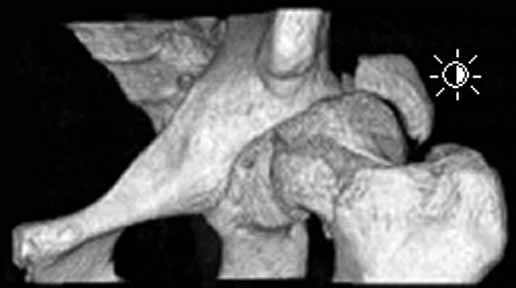

Here are some interesting plain films and CT images for a 22 yo male involved in an auto accident who was then struck as a pedestrian when he exited the vehicle.

3D-CT

He has a left sided sacroiliac injury with an associated posterior iliac fracture, femoral head fracture, femoral neck fracture with extruded head-neck fragment, and posterior wall acetabular fracture with osteochondral impaction.